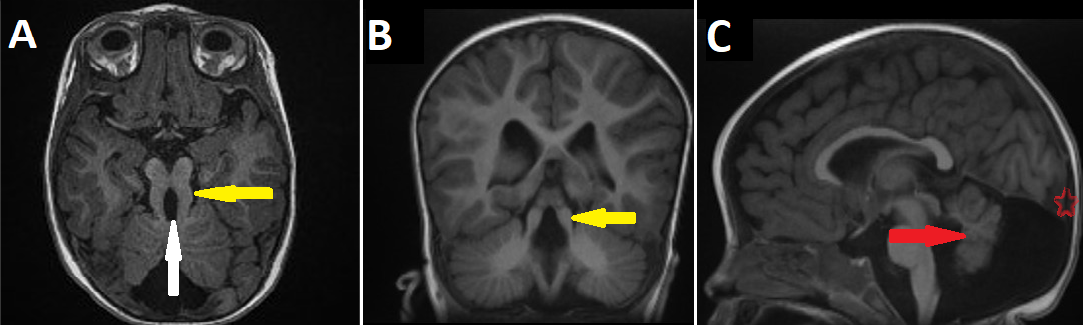

An 8-month-old infant was referred to our institution to investigate psychomotor retardation. The clinical finding found ataxia. An MRI was indicated and performed. Sequence T1 in the axial and coronal plane (A,B) revealed a long thick superior cerebellar peduncle (Yellow arrow) and an interpeduncular fossa (White arrow), reminding the molar tooth sign (MTS). Furthermore, sequence T1 in the sagittal plane (C) showed hypoplasia of the vermis (Red arrow) and global ascension of the tentorium cerebelli (Red star). Finally, the diagnostic of Joubert syndrome associated with Dandy walker malformation was confirmed by pathognomonic imaging. The family patient was informed and received the best medical assistance. Joubert syndrome is a rare recessive ciliopathy, diagnosed by a triad in cross-sectional imaging (Scanner / MRI). (1) thick and straight superior cerebellar peduncles, (2) deep interpeduncular fossa, and (3) hypoplastic/dysplastic vermis forming the "molar tooth sign". Dandy-walker syndrome is defined as rare malformation, presented in MRI as upward displacement of the tentorium, torcular and lateral sinuses and anterior-posterior enlargement of the posterior fossa. In effect, the association between the Joubert syndrome and Dandy-Walker malformation is even rarer. Joubert syndrome is often combined with liver, renal and eye disease. Its treatment is cumbersome as well as multidisciplinary depending on the organs affected, hence imaging is important to the precise diagnosis, thereby reduction its medical complications.